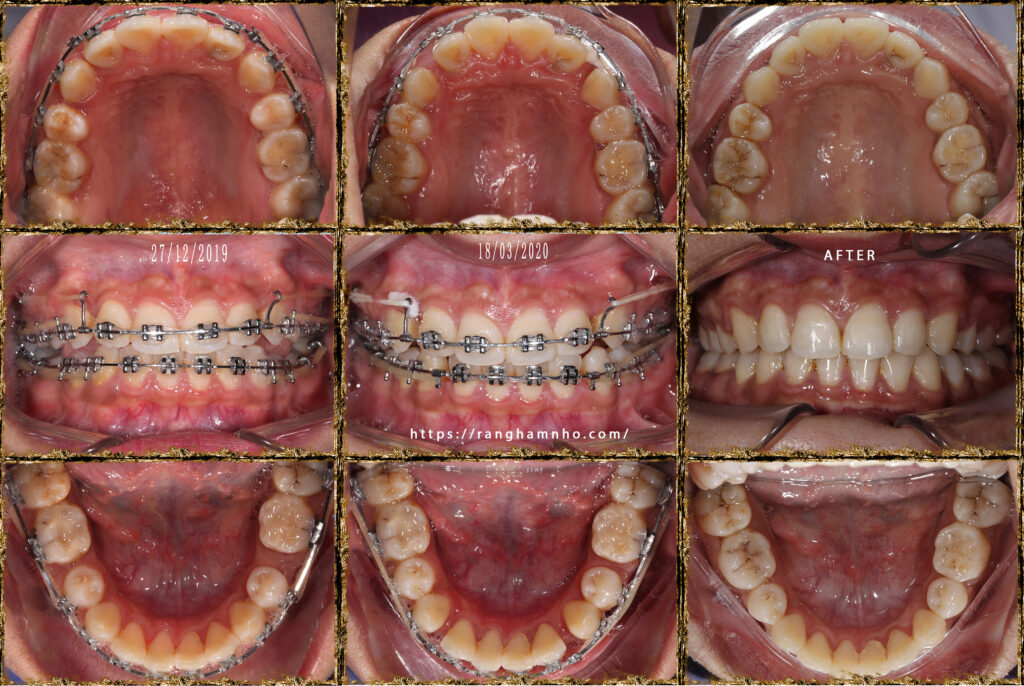

Chẩn đoán trước điều trị: sai khớp cắn hạng II, mặt hô, khớp cắn sâu. Chỉ định niềng răng nhổ 4 răng số 4 để kéo lùi nhóm răng cửa giảm hô tối đa. Có sử dụng neo chặn tuyệt đối bằng minivis chỉnh nha.

Tổng thời gian điều trị: 2 năm